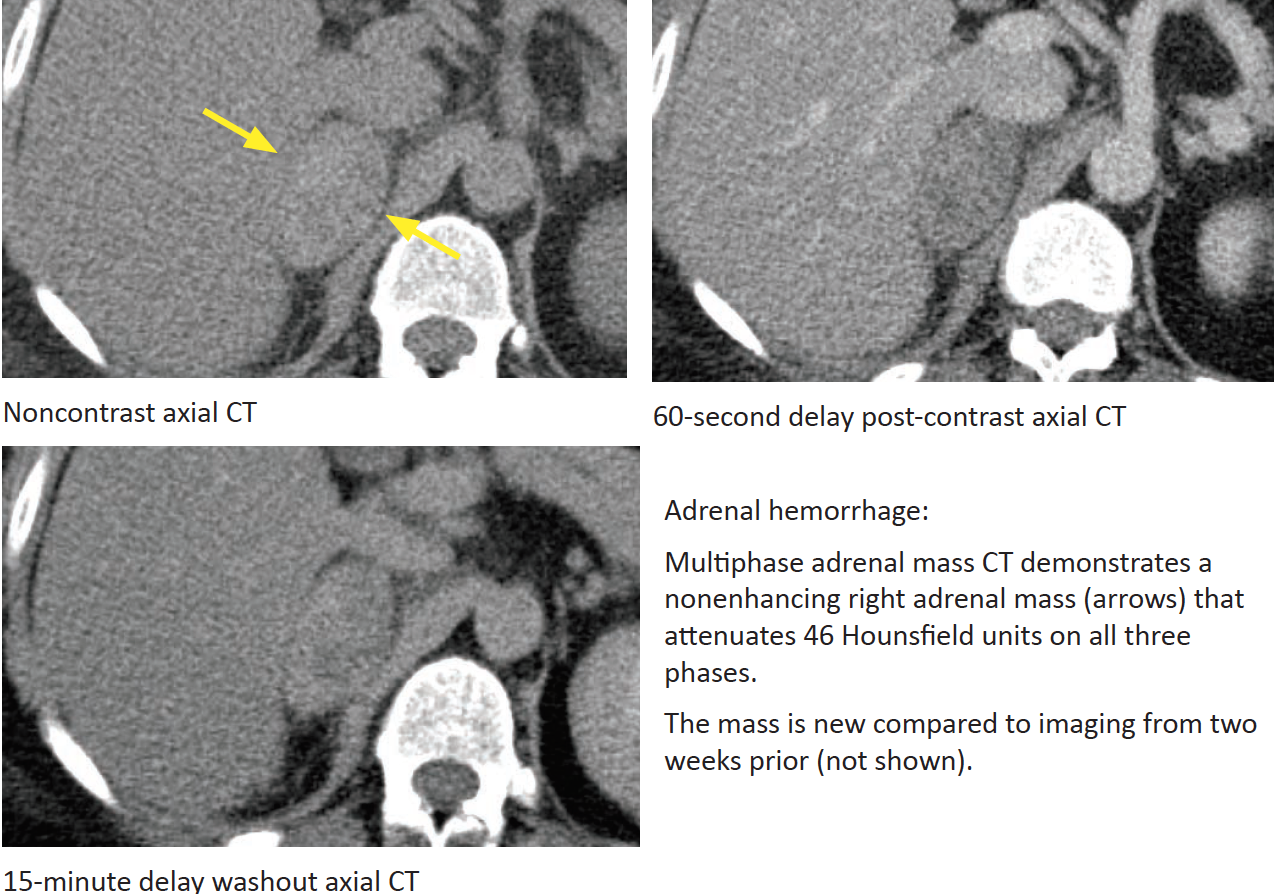

Adrenal Hemorrhage

What are the causes? If it is caused by anticoagulation when does it typically occur?

Which adrenal gland is more commonly involved?

Appearance? Most important clue?

Does it enhance? What would it look like on follow-up studies?